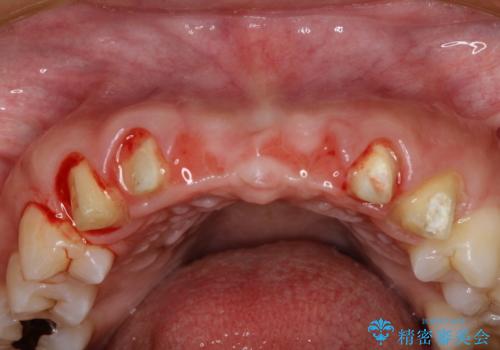

[ テトラサイクリン歯 ] 長年気になっていた変色歯を改善

- 長年気になっていた歯の変色を希望され来院されました。

他院でホワイトニングを何度か試したものの、理想に近い歯の白さは得られず、セラミック治療を進めていくこととなりました。

クラウン治療は歯を削合する必要がありますが、歯の変色を抜本的に改善することができます。

また歯の神経を温存しつつ、歯並びもある程度改善することが可能です。